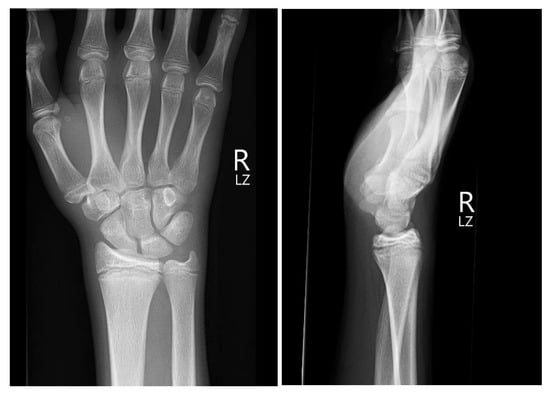

For the treatment of both the scaphoid fracture and distal radius fracture, we opted for a conservative approach involving immobilization of the wrist and thumb without immobilization of the IP joint of the thumb in a plaster, for a duration of 6 weeks. Upon follow-up X-ray after surgery, only small residual fragments of the pisiform bone were observed (Figure 5), with no evidence of secondary dislocation of the scaphoid or phalangeal fracture of the thumb. Physical therapy, involving gentle mobilization of the wrist, commenced immediately following the removal of the plaster cast. Given the absence of tenderness over the fractured bones, we decided to initiate exercises under loading in the subsequent 2 weeks.

Figure 5.

The follow-up X-ray (anteroposterior view on the left, lateral view in the middle, and 30° supination view on the right) after surgery revealed only small remaining fragments of the pisiform bone (depicted on the right image).